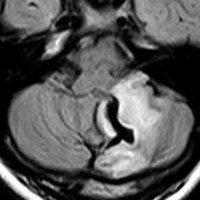

思春期の女の子にできた小脳腫瘍です。とても大きく見えますがほとんどが水たまり(のう胞といいます)。第4脳室が腫瘍で圧迫されて閉塞性水頭症になりました。のう胞の中に出血がありますが毛様細胞性星細胞腫では腫瘍内出血をしばしば見ます。右の写真で脳室が大きくなっています。こんなに大きいのに小脳症状は全くなくて,頭痛と嘔吐が症状でした。

赤で塗ったところだけが毛様細胞性星細胞腫です。これを取れば治ります。簡単な手術ですし後遺症も残りません。

手術後のMRIです。水頭症も改善してますから症状も消失しましたし,すぐに退院です o(^o^)o